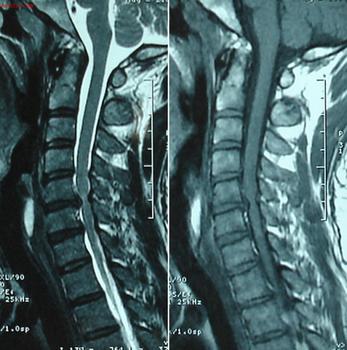

对强直患者常见的检查方式是做CT检查,观察的部位主要是人体的骶髂关节,如果身体的骶髂关节出现异常,出现炎症病变的话,结合身体症状可以对这种疾病初步确诊。

另外强直病人还要进行X线检查,对病变疼痛部位观察如果受关节部位的边缘模糊,或有明显的变形融合现象,则可对病情进行判定。主要观察位置除了腰背部位外,还是骶髂关节。